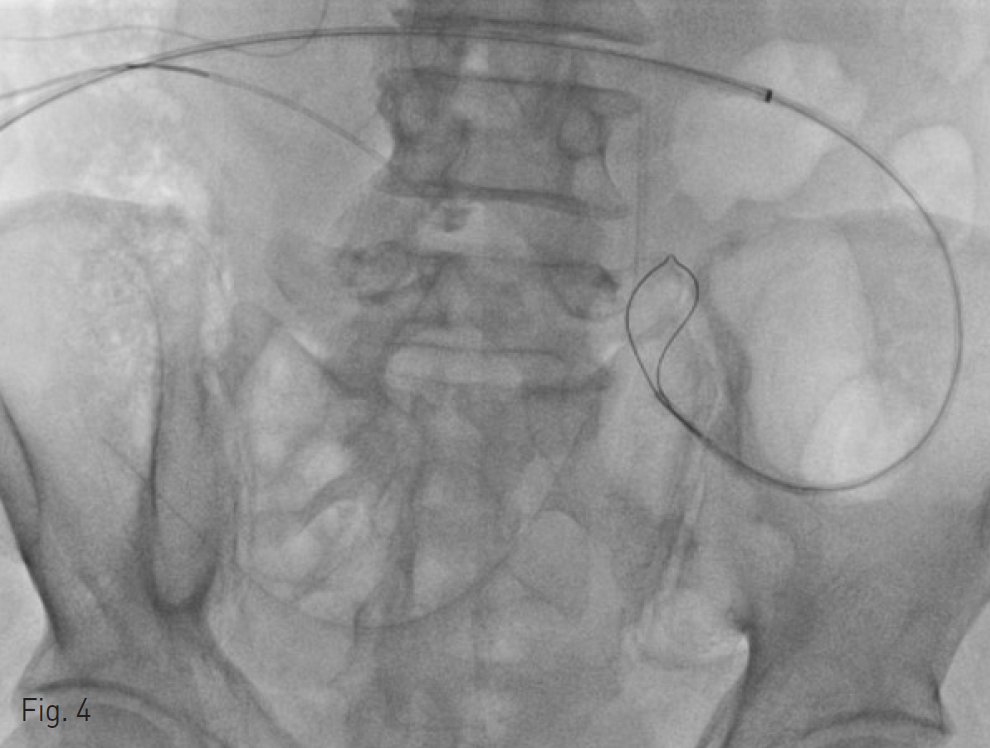

Fig. 4. Loosening of snare to release small bowel or mesentery, which was possibly captured by the snare